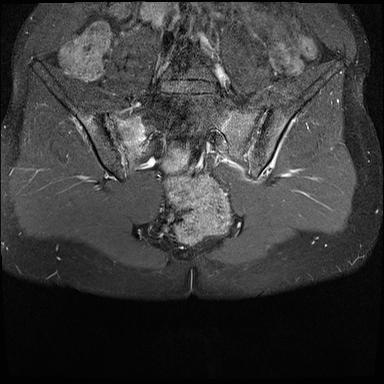

MRI

MRI chuỗi xung T1W sau tiêm thuốc tương phản từ của cùng bệnh nhân cho thấy bờ khớp cùng chậu không đều do bào mòn.

Có ngấm thuốc ở xương dưới sụn và phù nề tủy xương.

Không có tràn dịch khớp.

Thuốc tương phản từ tiêm tĩnh mạch không nhất thiết phải sử dụng để chẩn đoán viêm khớp cùng chậu.

Cuộn qua các hình ảnh MRI và so sánh với các dấu hiệu trên X-quang (hình ảnh cuối cùng).